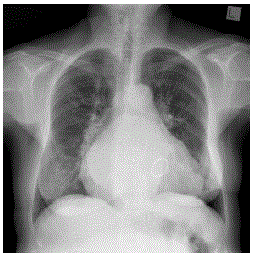

enunciado 1663588-1

Sobre ele, assinale a alternativa CORRETA.